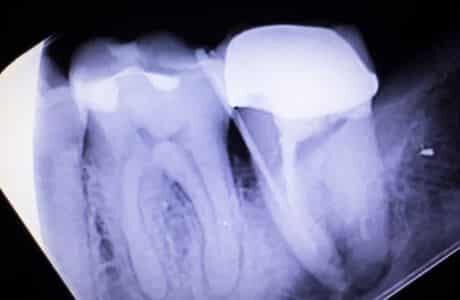

During a root canal, your dentist will first take an x-ray of your mouth to get an idea of what type of treatment you need. This step is important because it helps your dentist determine if there are any signs of infection or damage that they need to address during the procedure.

A root canal is a dental procedure that is done to remove the infected or decayed pulp from inside of a tooth. The purpose of this procedure is to save the patient’s natural teeth and avoid needing to get the tooth extracted. During a root canal, your Grand Junction Dentist will enter through the crown of the tooth and clean out any infection or decay present in the pulp. They will then fill in the space with material and seal it off so that it can be properly restored.

To ensure that no further damage occurs, your dentist may use files to shape the inside of your tooth before filling it up with a material such as gutta percha. This material helps keep bacteria from entering back into the area and causing additional damage down the line. Afterward, they may place a temporary crown over the area so that you can continue using it without pain until it heals completely.